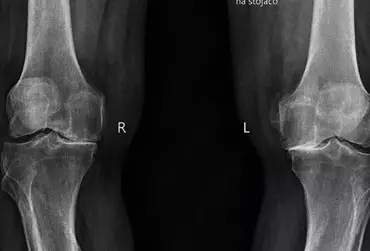

Endoprotezoplastyka stawu kolanowego — kompleksowa fizjoterapia szpitalna

Zwiększona aktywność fizyczna zarówno amatorska, jak i zawodowa może powodować wiele urazów, które w perspektywie czasu przyczyniają się do powstania rozmaitych chorób. Przeważnie choroba zwyrodnieniowa stawów przyczynia się do zmniejszenia ruchomości stawowej skutkującej różnorodnymi niedogodnościami. Schorzenie to stanowi również poważny problem nie tylko medyczny, ale również ekonomiczny. Zważywszy na fakt, iż jesteśmy społeczeństwem starzejącym się, z pewnością problem z roku na rok będzie się pogłębiał.

Kompleksowa aktywność fizyczna zarówno amatorska, jak i zawodowa jest dominującą częścią naszego życia. Odpowiednio wykonywana zapewnia prawidłowy oraz harmonijny rozwój całego organizmu. Ruch pod różnymi postaciami wpływa pozytywnie na wiele narządów i układów. Pod wpływem różnorodnych ćwiczeń stawy, zwłaszcza narządu ruchu, pozostają we właściwej kondycji. Staw kolanowy jest narażony na liczne urazy oraz choroby. Zwłaszcza choroba zwyrodnieniowa upośledza jego odpowiednie funkcjonowanie. W perspektywie czasu doprowadza w dużej mierze do uszkodzenia określonych struktur, np. chrząstki stawowej.